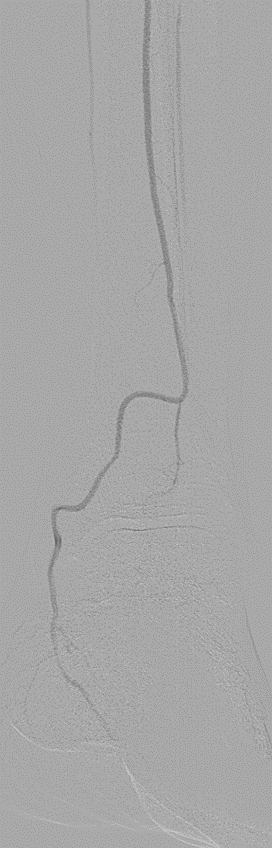

★ Case 9

FP long lesions below the Knee

左右滑动查看